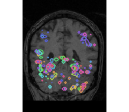

face

vs house

TV-l1

Graph-net

Social sparsity

Experiments outline a tradeoff between prediction accuracy and computation time. Fig. 1 displays the relative prediction accuracy and run time. TV- predicts best on average over the various classification tasks. However, it is followed closely by social sparsity which outperforms graph-net222All differences are significant in a Wilcoxon rank test.. The SVM performs much worse than the spatial sparsity, aside from the VBM data where we find that all models perform similarly.

Finally, an important aspect of the brain decoders is whether they segment well the brain regions that support the decoding. Such a question is hard to validate, yet there is evidence that TV- is a good approach [5]. Fig. 2 displays the decoder maps for the object-recognition tasks. For these tasks, we expect prediction to be driven by the functional areas of the visual cortex [27]. Indeed, the maps outline regions in known visual areas. The graph-net maps are much more scattered and less structured than the others. Conversely, the social sparsity maps are sparser and outline a smaller number of clusters.